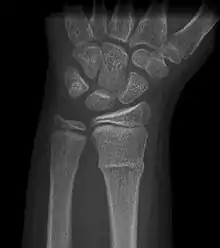

A Torus fracture, also known as a buckle fracture is the most common fracture in children.[1] It is a common occurrence following a fall, as the wrist absorbs most of the impact and compresses the bony cortex on one side and remains intact on the other, creating a bulging effect.[2] As the bulge is only on one side of the bone, this injury can be classified as an incomplete fracture. The compressive force is provided by the trabeculae and is longitudinal to the axis of the long bone, meaning that the fracture itself is orthogonal to that axis.[3] The word "torus" originates from the Latin word "protuberance."[4]

Buckle fracturs can be identified by performing a radiograph. The diagnosis of a torus fracture is made from both anterior/posterior and lateral projections. The typical features include:

- The buckling of cortical bone, which may appear as a small bulge or protuberance in the radius or ulna.

- The bone may have a slight angulation.[8]